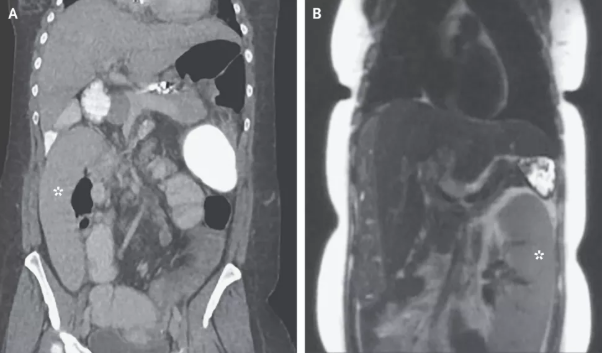

密歇根醫(yī)學院內(nèi)科醫(yī)生Alexander Wester博士介紹,脾臟是人體內(nèi)負責過濾血液并提供免疫力的器官,通常位于腹部左上位置,胃部上方。但是,這名36歲婦女的影像學結(jié)果顯示,她的脾臟出現(xiàn)在了腹部右下位置。

巧合的是,這名婦女剛剛做了肝癌篩查,影像學報告中的脾臟還是正常的,位于身體左側(cè)(圖B)。她檢查之后的第一天出現(xiàn)了腹痛和嘔吐,第二天再做一次檢查,脾臟向右跑了0.3米(圖A)。